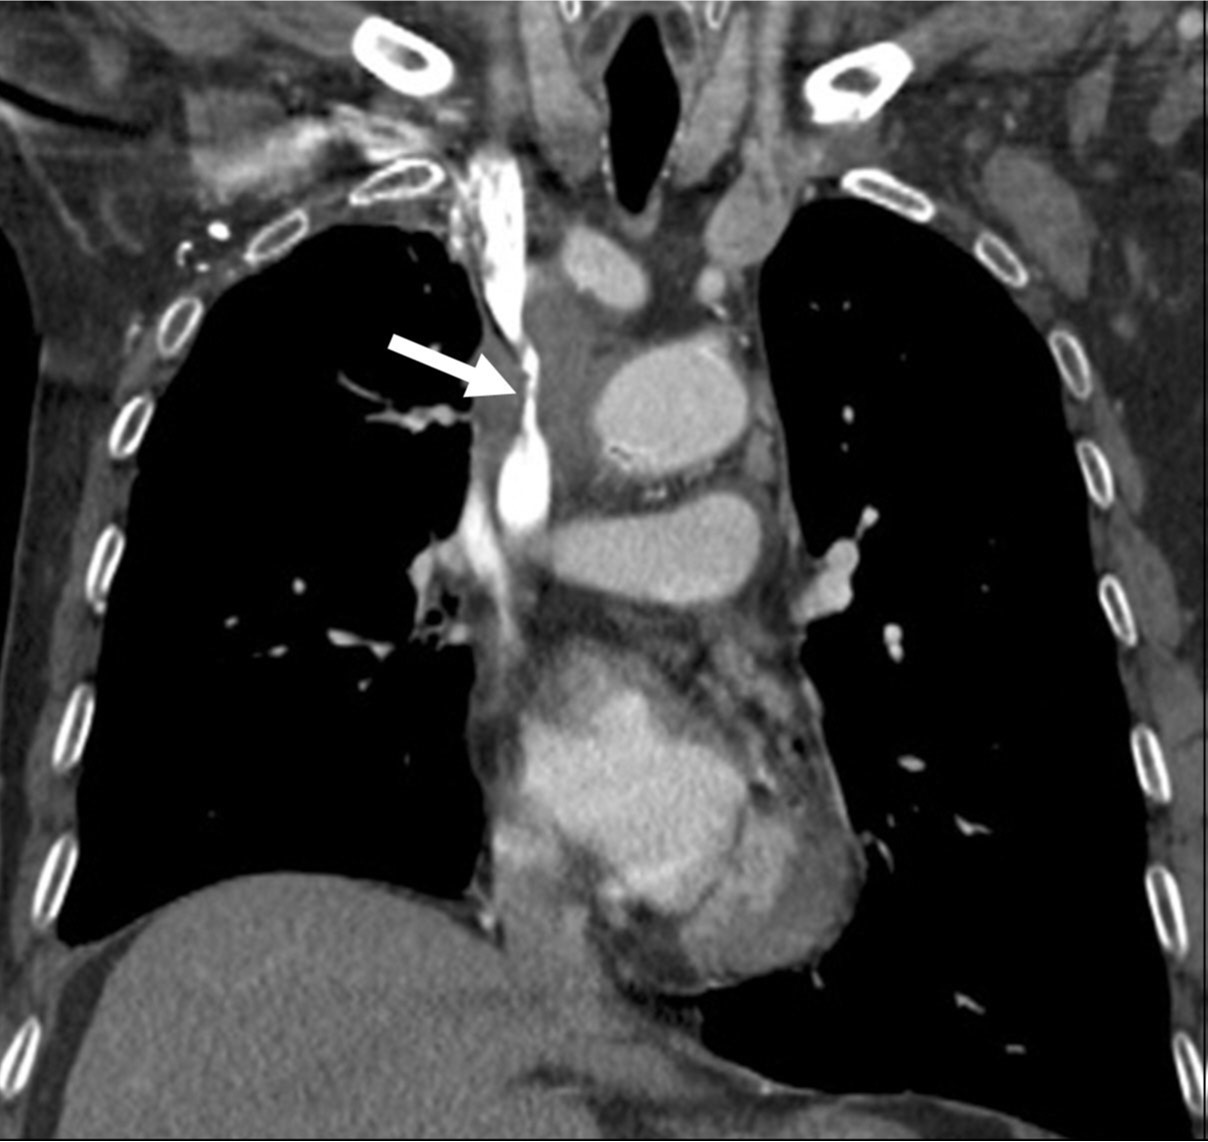

Fig. 1. A

Fig. 1A, 1B. The axial (A) and coronal (B) images of chest CT scans show segmental severe narrowing(arrows) of the superior vena cava resulting from compression by the surrounding malignant tumor with mediastinal lymph node metastasis.

Fig. 1. B